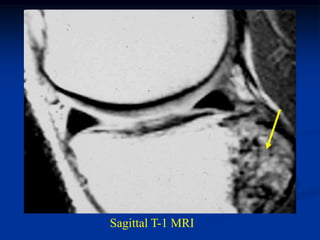

Case #589

16 year male

periosteal chondroma

distal femur

AP view